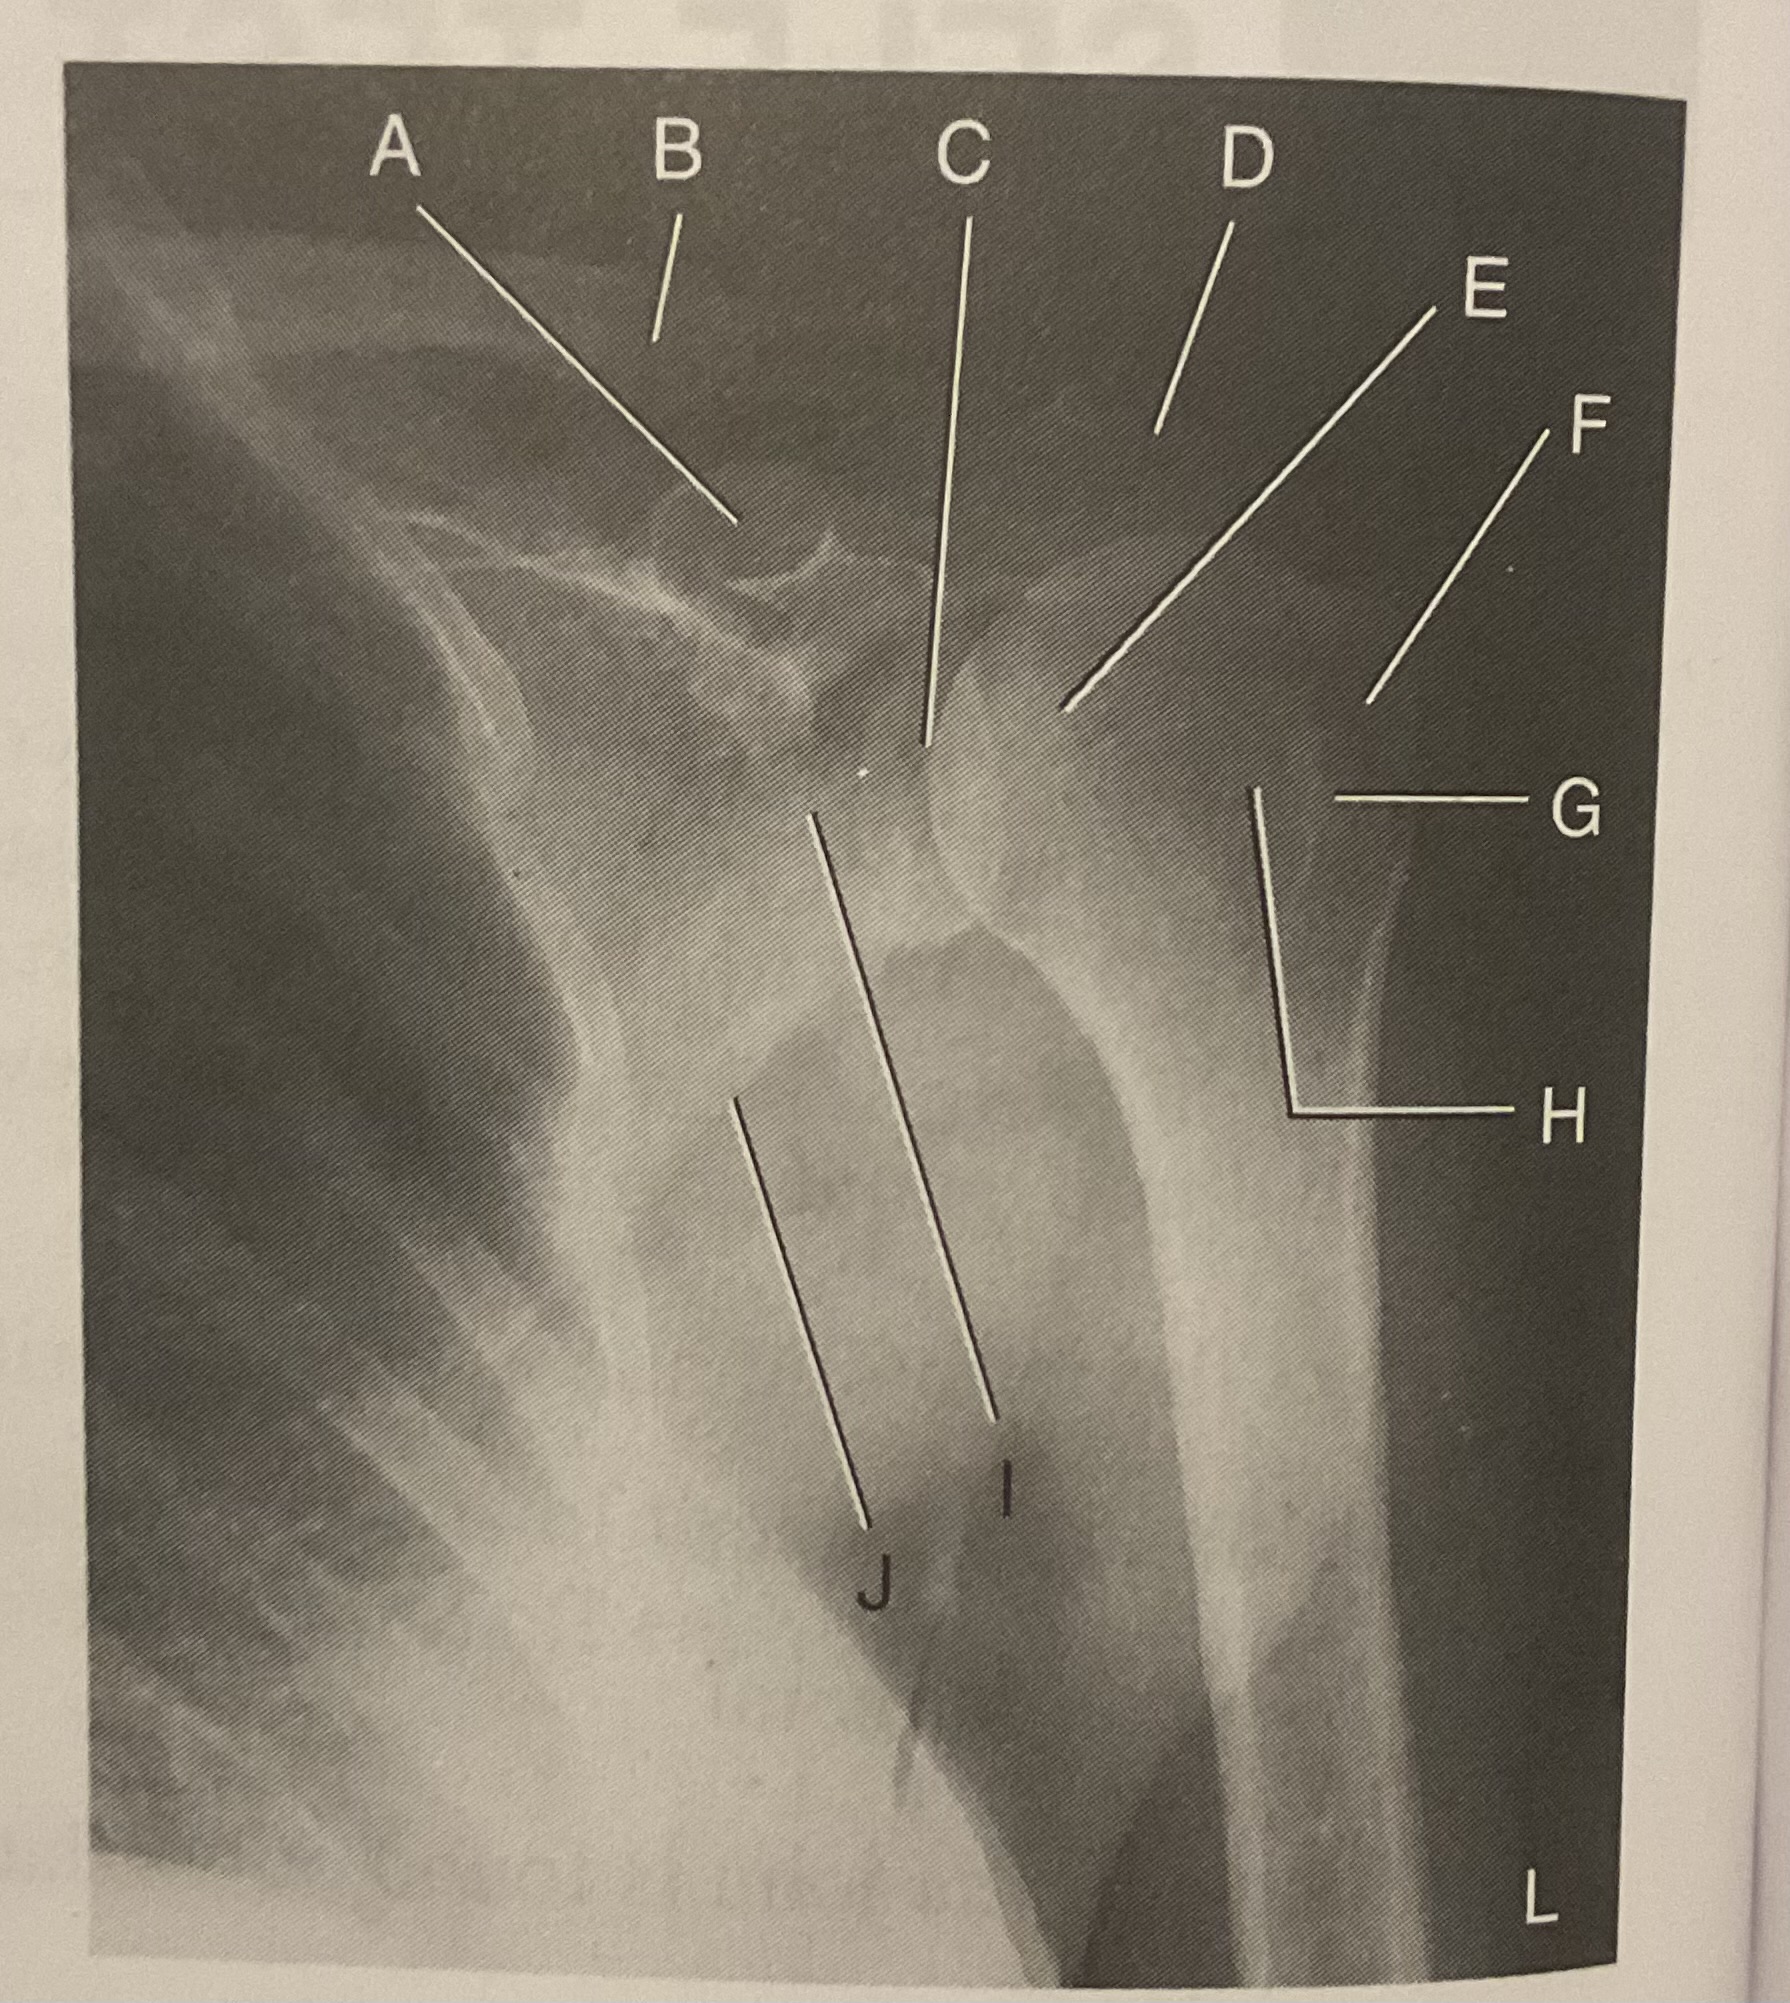

A?

Coracoid process

B?

Clavicle

C?

Scapulohumeral joint

D?

Acromion of scapula

E?

Head of humerus

F?

Greater tubercle

G?

Intertubercular sulcus

H?

Lesser tubercle

I?

Neck of scapula

J?

Lateral (axillary) border of scapula

What AP projection does this image represent?

External